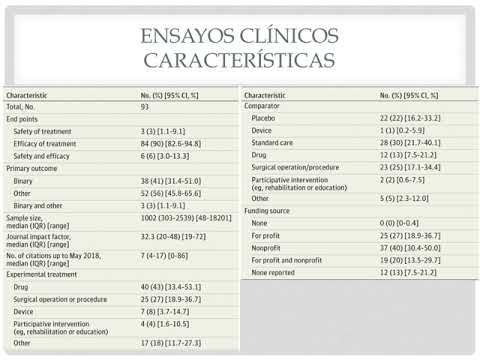

Nivel y prevalencia de spín en informes publicados de ensayos clínicos aleatorizados con resultados primarios estadísticamente no significativos: una revisión sistemática. Dra. Florencia Cichello. Residencia de Cardiología. Hospital C. Argerich. Buenos Aires